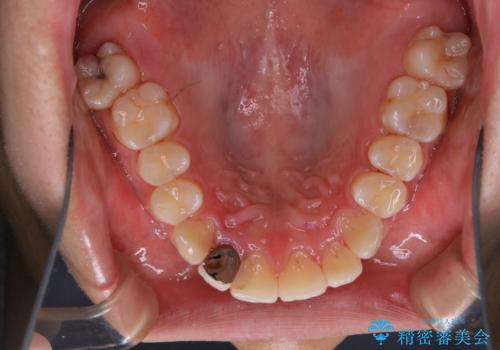

- 10年ぶりの歯科とのことで、全体の検診希望で来院されました。レントゲン撮影、歯周ポケット検査、ブラッシング指導、クリーニングを行いました。

今回はお口全体にプラーク(細菌の塊)、歯石、着色(ステイン)が付着していたため、検査後、歯科衛生士による専門的自費のPMTC(クリーニング)60分コースを行いました。

まずは、お口全体の染め出しをし、どこに汚れや磨き残しが多くついているかを明確にしました。その後、普段の歯磨きの仕方の確認や、ブラッシング指導をしました。

10年ぶりの歯科医院へ来院とのことで全体的に汚れ(バイオフィルムや着色)が多く付着してたため、自費クリーニングPMTC60分コース10000+TAXを行いました。